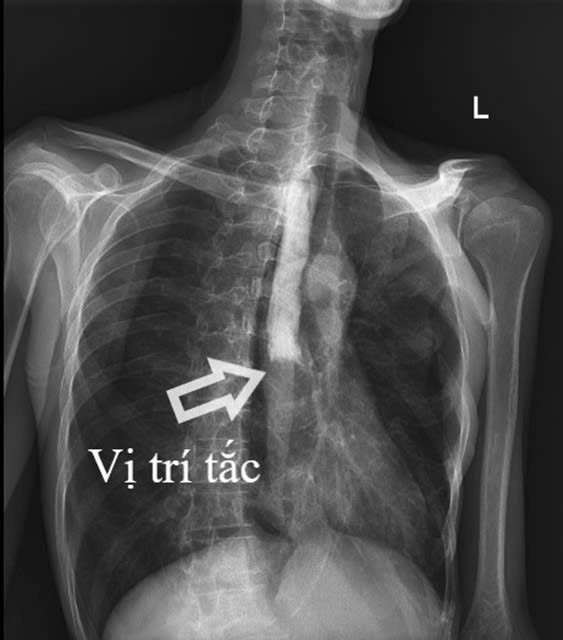

Kết quả cận lâm sàng cho thấy hình ảnh tắc thực quản hoàn toàn đoạn 1/3 giữa và viêm lan tỏa dạ dày, ruột non, viêm phúc mạc do thủng tạng rỗng.

Đây là một thách thức lớn đối với đội ngũ bác sĩ vì tổn thương xuất hiện ở nhiều vị trí (thực quản, dạ dày, ruột non), gây khó khăn trong việc xác định chính xác nguyên nhân gốc rễ là do Lao, Ung thư (Lymphoma) hay bệnh lý tự miễn (Crohn)